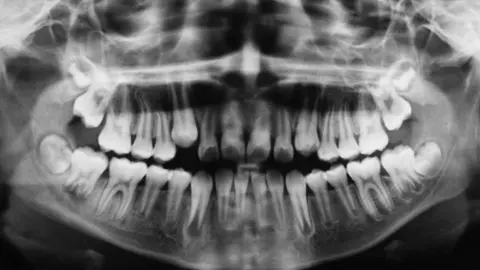

El origen del Alzhéimer podría estar relacionado con una enfermedad bucal

Así lo refuerza un nuevo estudio publicado en Science Advances que relaciona ambas enfermedades